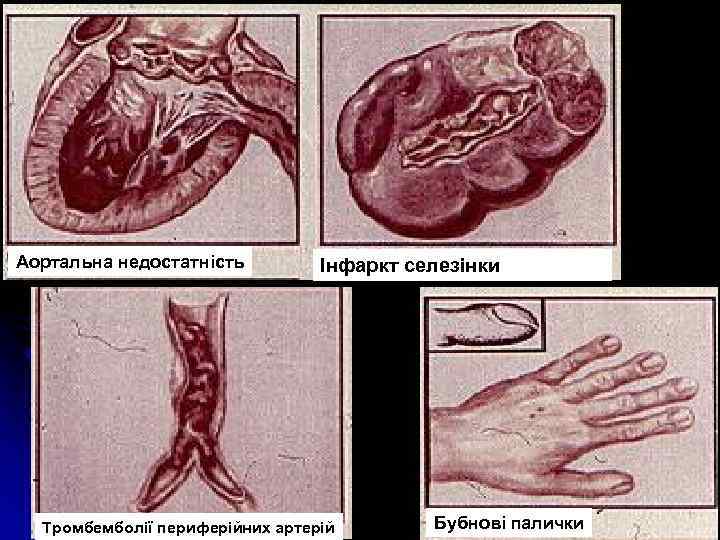

Аортальна недостатність Інфаркт селезінки Тромбемболії периферійних артерій Бубнові палички